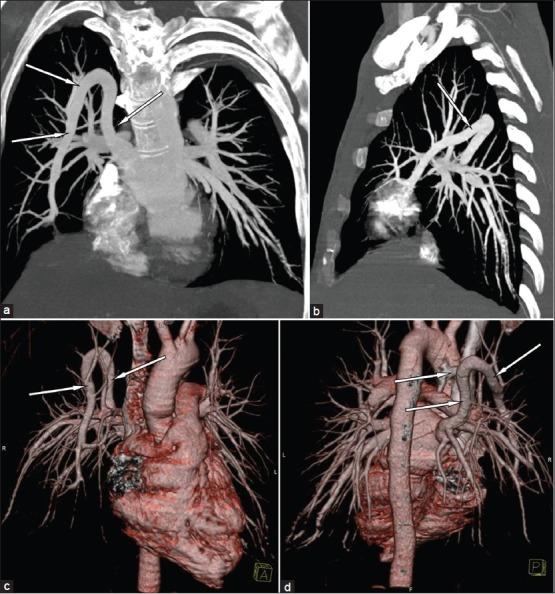

The pulmonary venous abnormalities are very rare and are difficult to diagnose. We present a case of middle age male who presented with cough and chest pain. Chest radiograph showed abnormal tortuous vessel in right lung. Computed tomographic angiography of chest demonstrated meandering anomalous right superior pulmonary vein.

https://cdn.ncbi.nlm.nih.gov/pmc/blobs/a4d6/3519023/ed104ff1a564/LI-29-363-g001.jpg